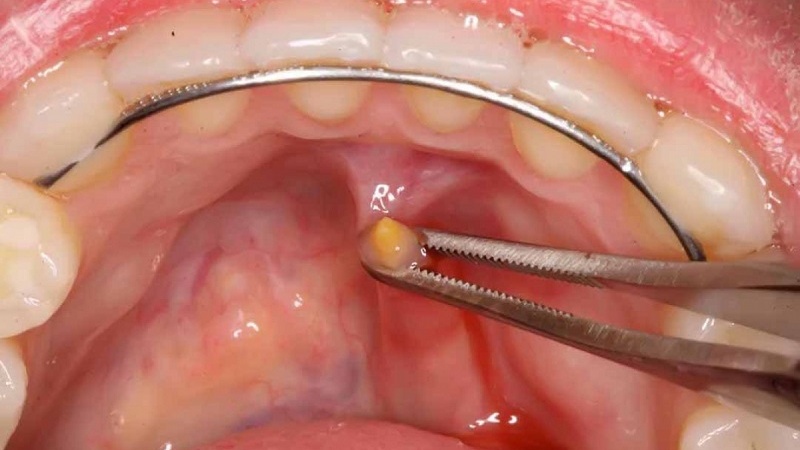

Lý do phổ biến nhất đằng sau quyết định phẫu thuật thường là do ống dẫn nước bọt bị tắc nghẽn. Tình trạng này có thể phát sinh từ sỏi trong ống dẫn nước bọt hoặc do sự hẹp bẩm sinh của ống dẫn nước bọt. Việc tắc nghẽn ống dẫn nước bọt có thể gây đau và sưng ở khu vực tuyến dưới hàm khi ăn.

Nếu sỏi kẹt trong tuyến dưới hàm, tuyến có thể trở nên sưng và viêm nhiễm kéo dài, tạo ra sự không thoải mái trong thời gian dài. Do đó, nếu cần thiết, bác sĩ có thể đề xuất phẫu thuật cắt bỏ tuyến dưới hàm.